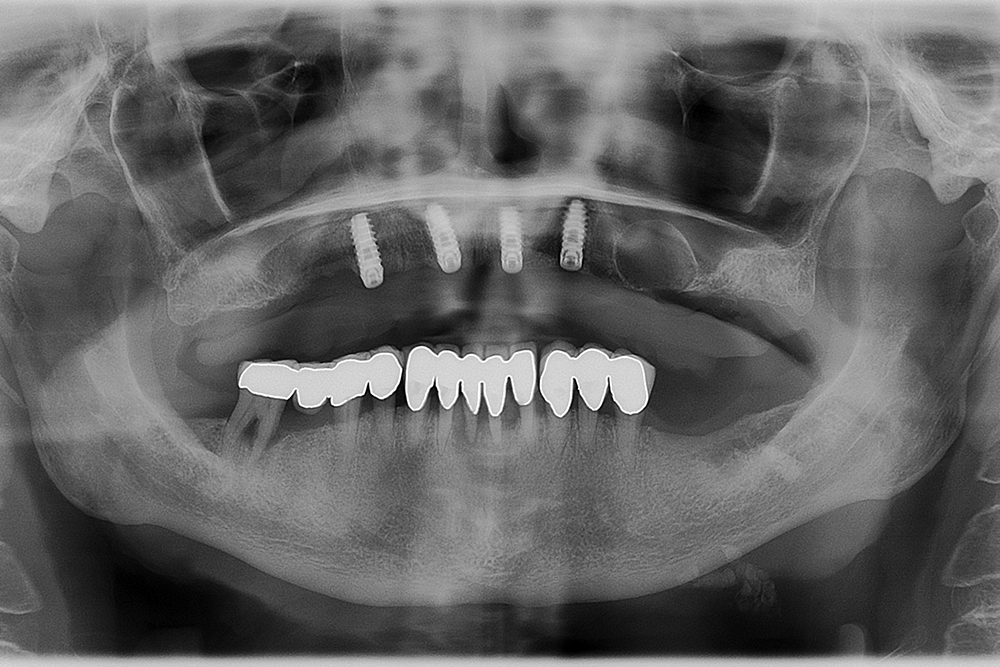

Ripristino dell’arcata superiore su overdenture su barra